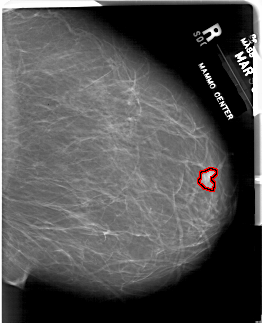

FILE: A_1815_1.RIGHT_MLO.OVERLAY

TOTAL_ABNORMALITIES 1

ABNORMALITY 1

LESION_TYPE MASS SHAPE TUBULAR MARGINS CIRCUMSCRIBED

ASSESSMENT 4

SUBTLETY 4

PATHOLOGY BENIGN

TOTAL_OUTLINES 1

BOUNDARY